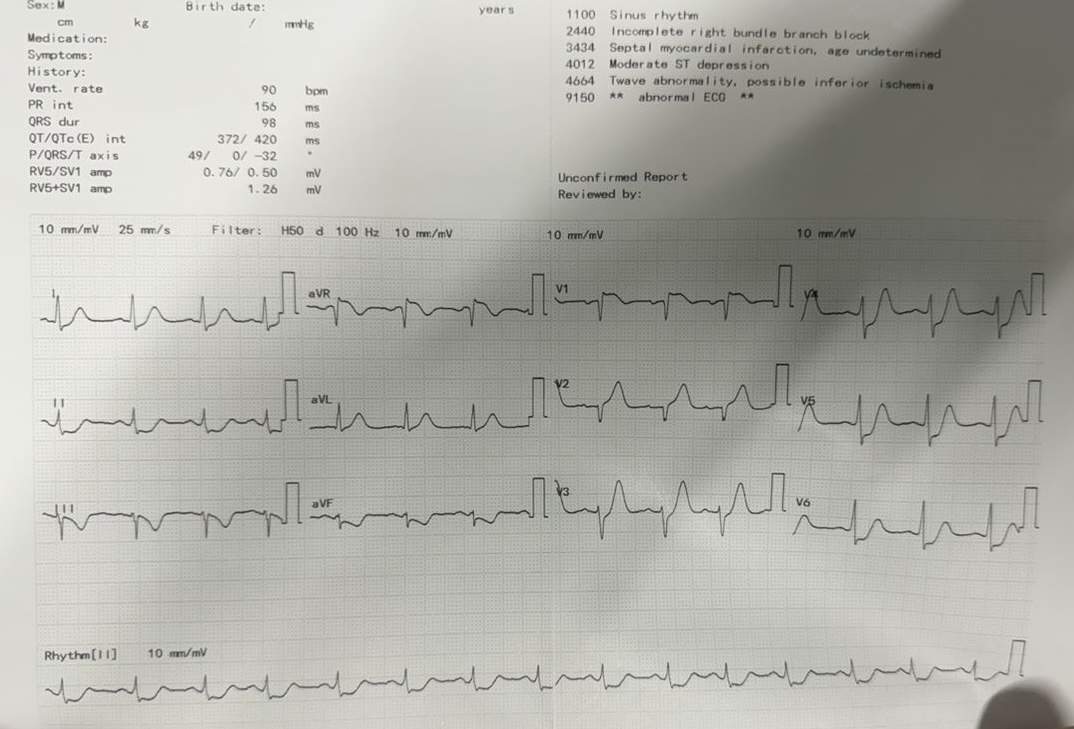

Electrocardiogram: ST elevation in aVR and V1 with widespread ST depressionEchocardiography: EF 60.4% with anteroseptal hypokinesia. No significant valvular abnormalities.